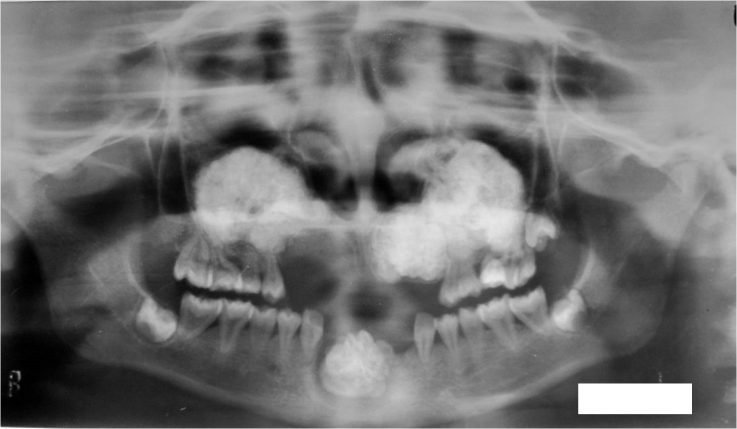

В некоторых случаях возникает ситуация, когда корни верхних зубов расположены в непосредственной близости к гайморовым пазухам, что приводит к постоянным болям в верхней челюсти у человека, страдающего гайморитом.

- Развитие кариеса верхних зубов. Метод рентгенограммы носовых пазух позволит определить степень поражения зубов и возможность их удаления без осложнений.

- Операция по имплантации зубов. Для определения места посадки зубного импланта и наличия патологий проводится носа.

Рентгенографические признаки одонтогенного гайморита

Заболевания зубов верхней челюсти являются основной причиной развития одонтогенного гайморита. Рентгенологическое обследование показывает наличие затемнений в области пазух, а также патологические изменения в лунках зубов и утолщение костей верхней челюсти.

- У детей часто причиной поражения костной перегородки является остеомиелит, возникновение которого связано с наличием кариозных зубов.